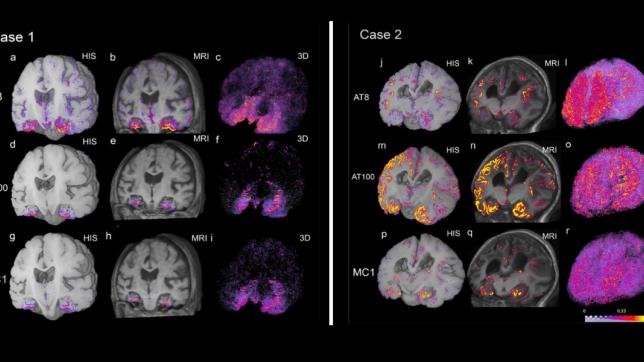

Team Develops Tau Aggregation Predictor to Model Progression of Alzheimer's Disease

News